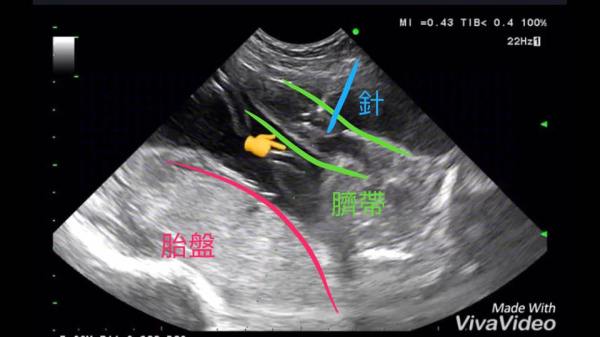

關於羊膜穿刺

BoBoCan寶貝幫x蘇醫師講古系列 有時候 用說的比用寫的簡單 我知道 很多沒做過的媽咪 即便聽過很多 但是... Continue Reading →

很多人都喜歡說 羊膜穿刺是最準確的 是百分之百準確的 真的是這樣嗎? 我從事了20多年這方面的工... Continue Reading →